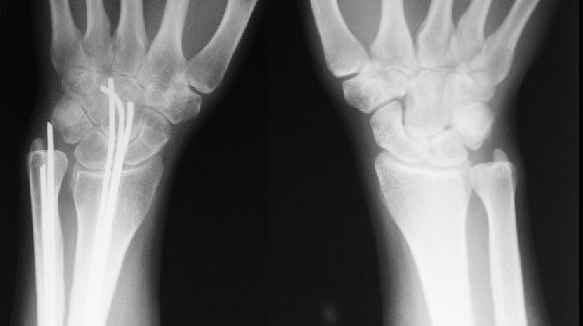

Сравнительные снимки в приложении